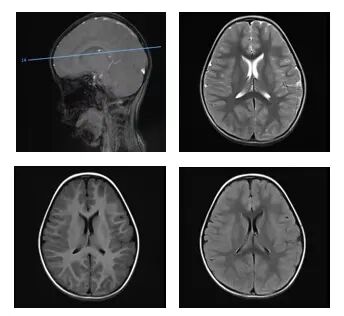

晓月在补液治疗时,渐渐出现嗜睡、意识模糊、双眼上翻凝视等症状,最后竟然陷入昏迷!紧急抢救后,她被送入重症监护室(PICU)。检查发现,她急性酒精中毒,出现了严重代谢性酸中毒、大脑功能受损。

△检查发现,患儿出现了颅内多发病变。